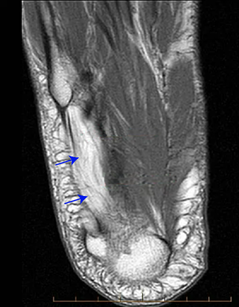

▶Baxter神经支配小趾展肌,其被卡压后小趾展肌存在病变,但临床上很难检测到,核磁共振可以确诊。

图17:核磁共振显示小趾展肌萎缩伴脂肪化